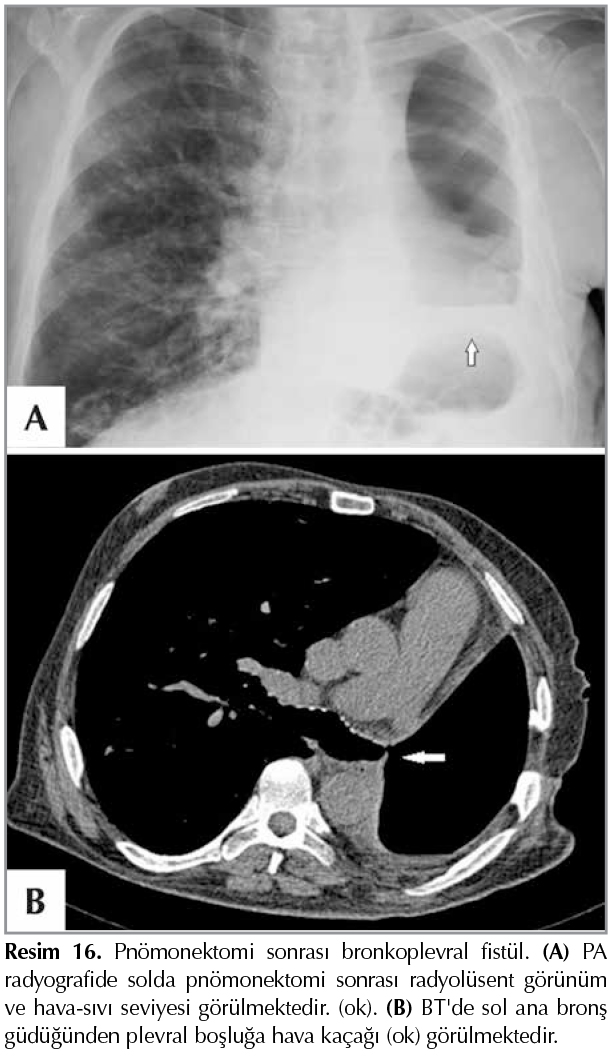

BPF yalnız cerrahi rezeksiyondan sonra değil, travma, infeksiyon, t?moral kitle ve radyasyon gibi nedenlerden dolayı da g?r?lebilir (18,33). BPF'de radyolojik bulgular (Resim 16):

Resim 16

a. Plevral boşlukta hava artışı,

b. Hava-sıvı seviyesi,

c. Hava-sıvı seviyesinde değişiklik g?r?lmesi,

d .Tansiyon pn?motoraks,

e. Mediastenin cerrahi girişimden ?nceki konumuna d?nmesi,

f. Aspirasyon pn?monisi bulguları (18,33,64).